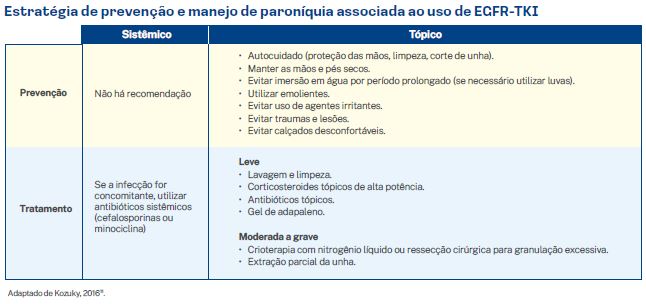

3.1.1. Paroníquia

A paroníquia é caracterizada por inflamação sensível, edematosa e muitas vezes purulenta da dobra ungueal. As unhas das mãos e dos pés podem ser afetadas. A morbidade é elevada, podendo acarretar em dor, limitação funcional e comprometimento das atividades da vida diária. Não existem tratamentos aprovados para alterações ungueais associadas aos EGFR-TKI, pois não houve estudos randomizados e controlados avaliando terapias para paroníquia. As recomendações baseiam-se na opinião de especialistas.